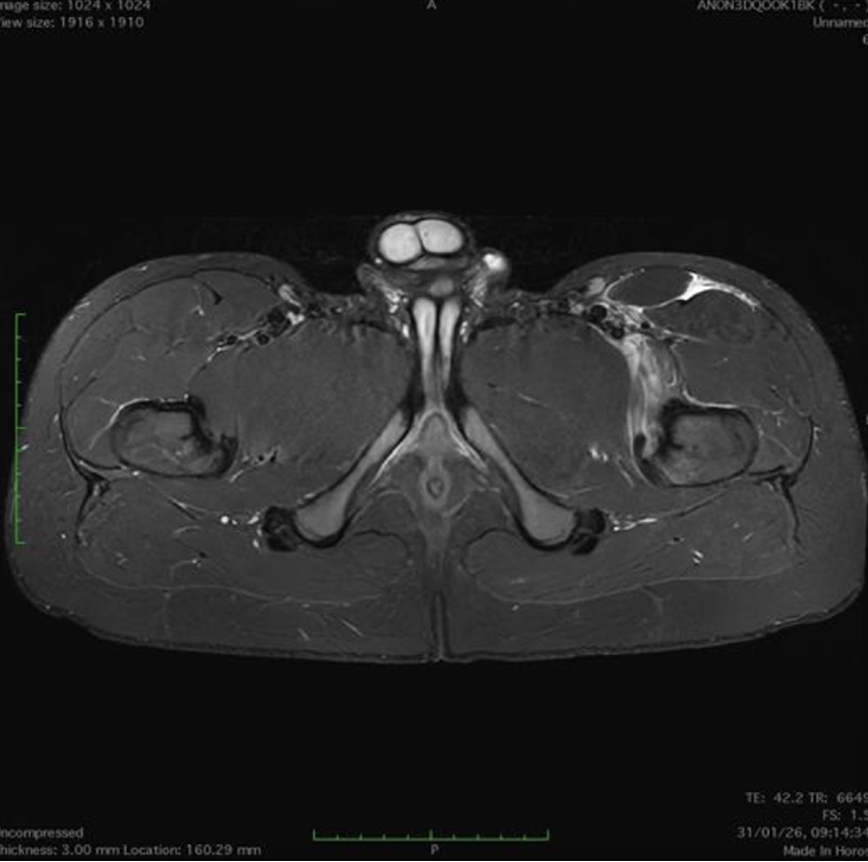

Paziente con anamnesi di malattia coronarica e pregresso impianto di stent sulla discendente anteriore sinistra.

Per prima cosa, esamina l'intera scansione. Concentrati sul tronco comune e sulla porzione prossimale della discendente anteriore sinistra.